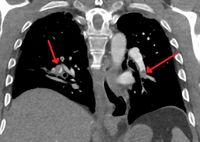

التصوير الطبقي المحوسب

التصوير الطبقي المحوسب للرئة والمصحوب باستخدام الصبغة المشعة في الوريد أصبح واسع الانتشار والاستخدام في تشخيص المرضى المشتبه بإصابتهم بالانصمام الرئوي، لهذا النوع من التصوير حساسية تبلغ 83% ودقة نوعية تصل إلى 96%.[24].[25]